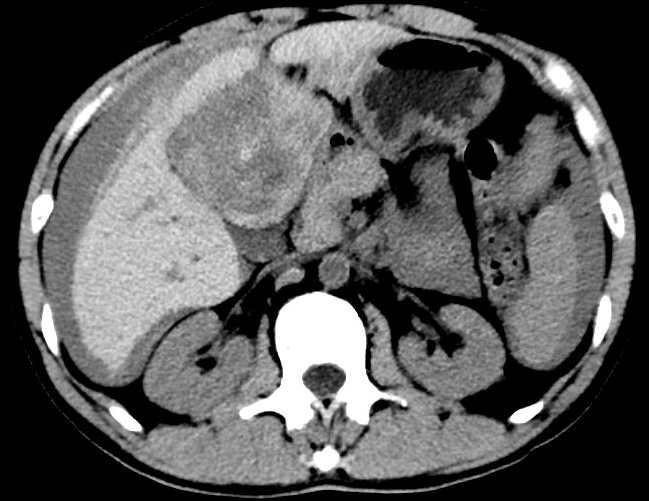

放下電話的白葦急赴消內(nèi)三搶救室會診,經(jīng)仔細(xì)查體、對患者腹部CT進(jìn)行詳細(xì)閱片、綜合評估患者后,考慮患者是肝占位破裂出血。患者病情十分緊急、一刻也不容耽誤,需立刻急診行肝動脈造影 栓塞術(shù)進(jìn)行止血治療,在與患者家屬溝通后,立即通知消化介入室準(zhǔn)備急診手術(shù)。

入手術(shù)室時,患者神志迷糊,口唇干燥、重度貧血貌,心電監(jiān)護(hù)提示:心率140-160次/分,血壓70/43mmHg,這是失血性休克的表現(xiàn)!白葦快速建立靜脈通道緊急給予輸血,升壓,止血等液,立即給予肝動脈造影,術(shù)中發(fā)現(xiàn)肝左葉疑似腫瘤病灶、病灶周圍血管分支有造影劑外溢,考慮血管破裂出血,迅速給予栓塞微球進(jìn)行肝動脈栓塞。整個手術(shù)過程不足20分鐘,術(shù)后即刻患者心率降至100-110次/分、血壓升至90/60mmHg。

術(shù)后給予積極抗炎,止血,保肝、利尿等對癥治療,復(fù)查血常規(guī)提示活動性出血停止后,在超聲引導(dǎo)下行腹腔穿刺引流術(shù),術(shù)后3天共引流出血性腹水約4000ml?;颊呓?jīng)復(fù)查各項(xiàng)指標(biāo)均趨于正常,復(fù)查CT提示腹腔積血已基本吸收,患者康復(fù)出院。